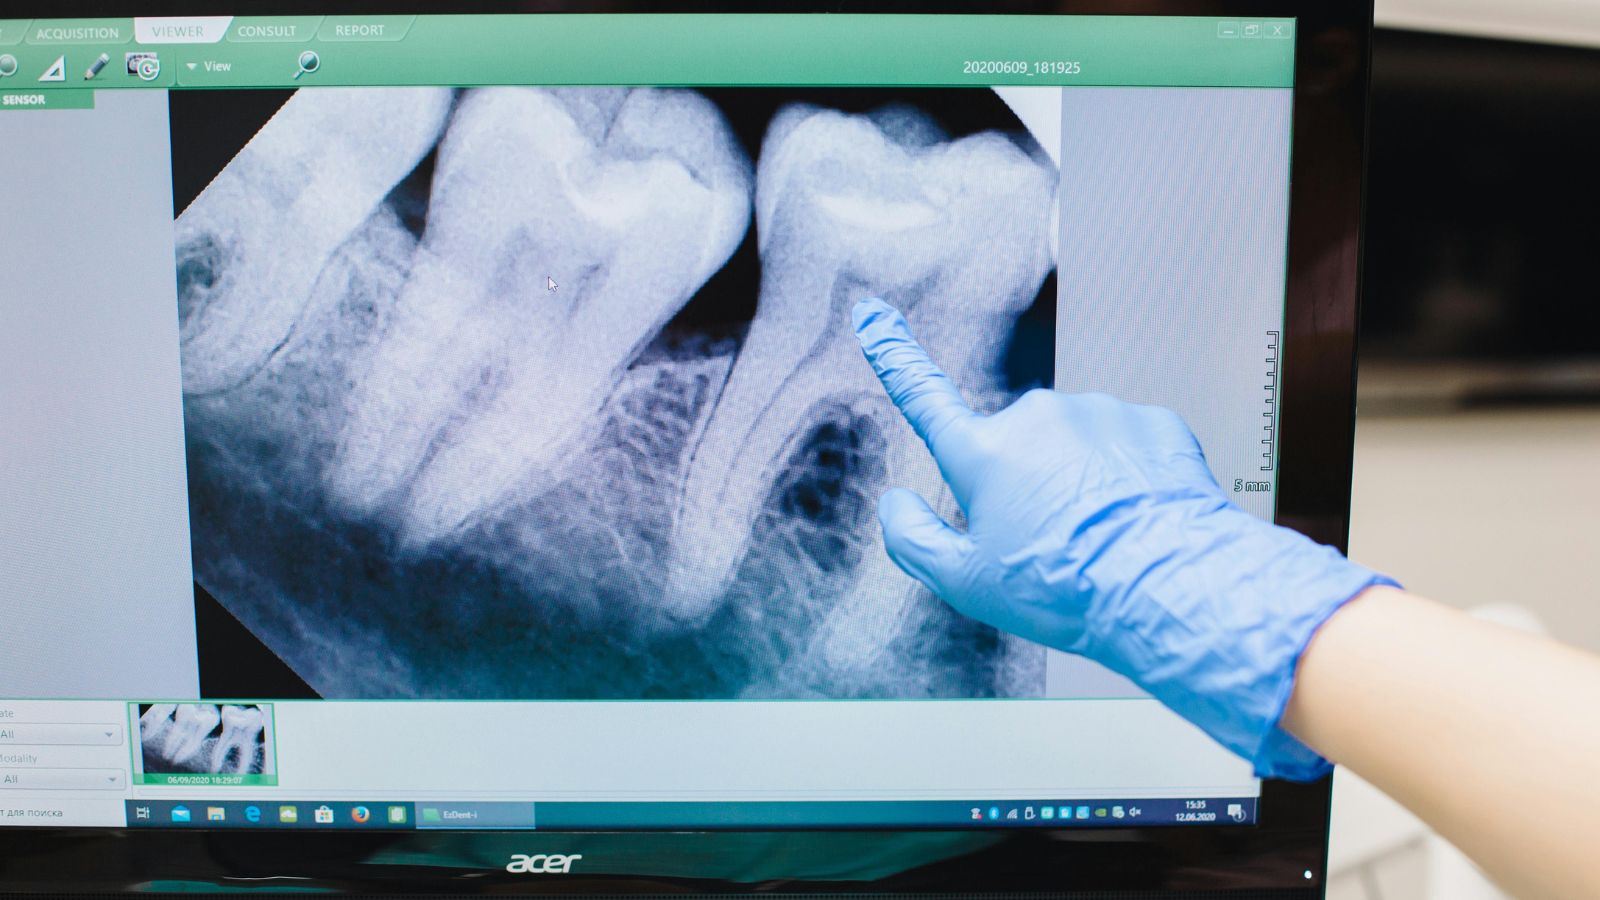

Decyzję o zabiegu zawsze poprzedza dokładna diagnostyka – najczęściej wykonuje się pantomogram (zdjęcie panoramiczne) lub tomografię komputerową (CBCT), by ocenić pozycję zęba i jego relację do sąsiednich struktur, takich jak nerw zębodołowy dolny czy zatoka szczękowa.